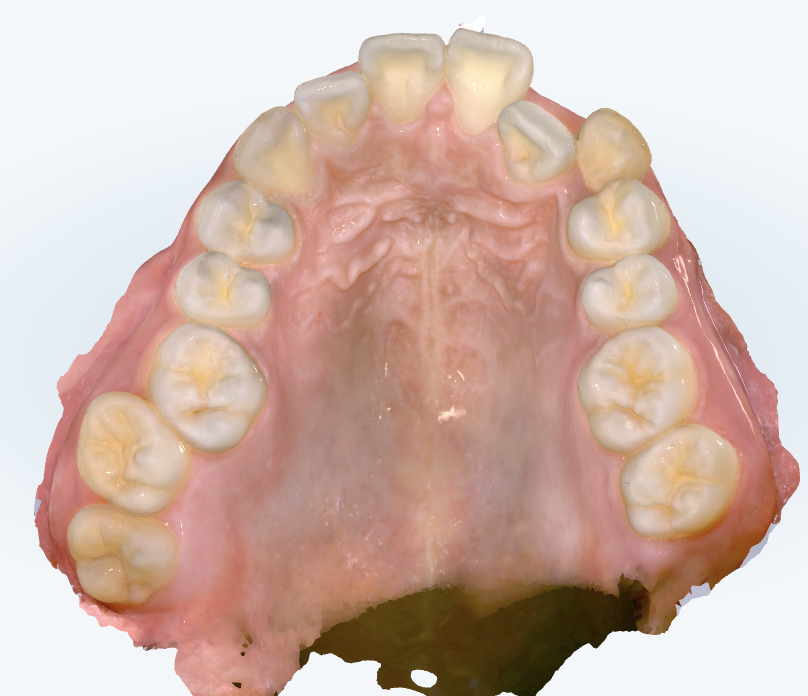

初診時の画像診断

上下の前歯は前後的に距離があり、出っ歯の傾向があります。奥歯の関係性も歯1本分出っ歯傾向です。

上下の歯並びにガタガタがあります。咬み合わせも深いです。右の奥歯は上下で噛み合っていない歯があります。

ガミースマイルです。